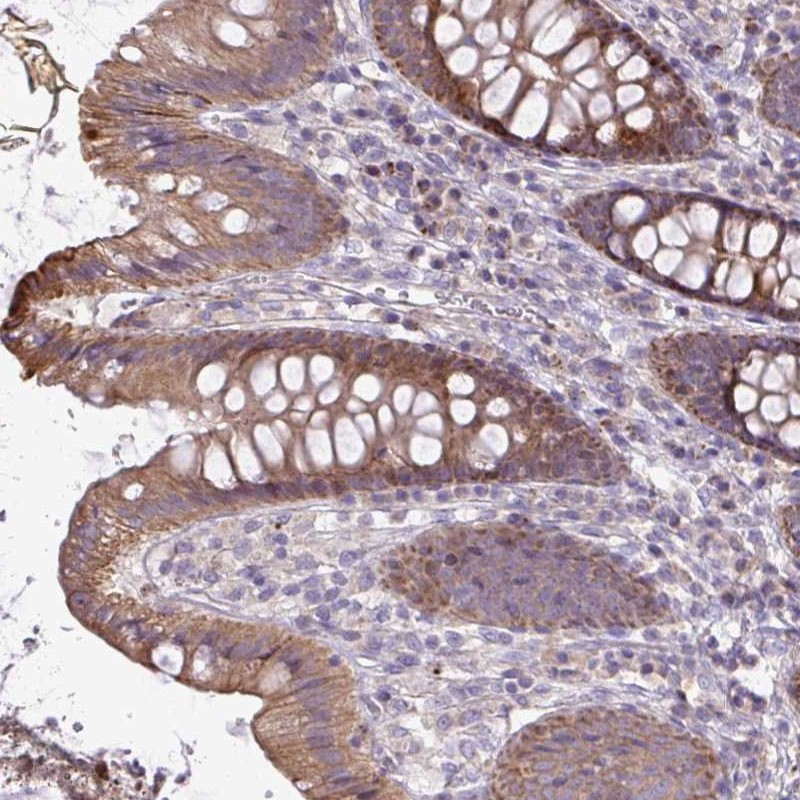

Immunohistochemical staining of human colon shows moderate cytoplasmic positivity in glandular cells.